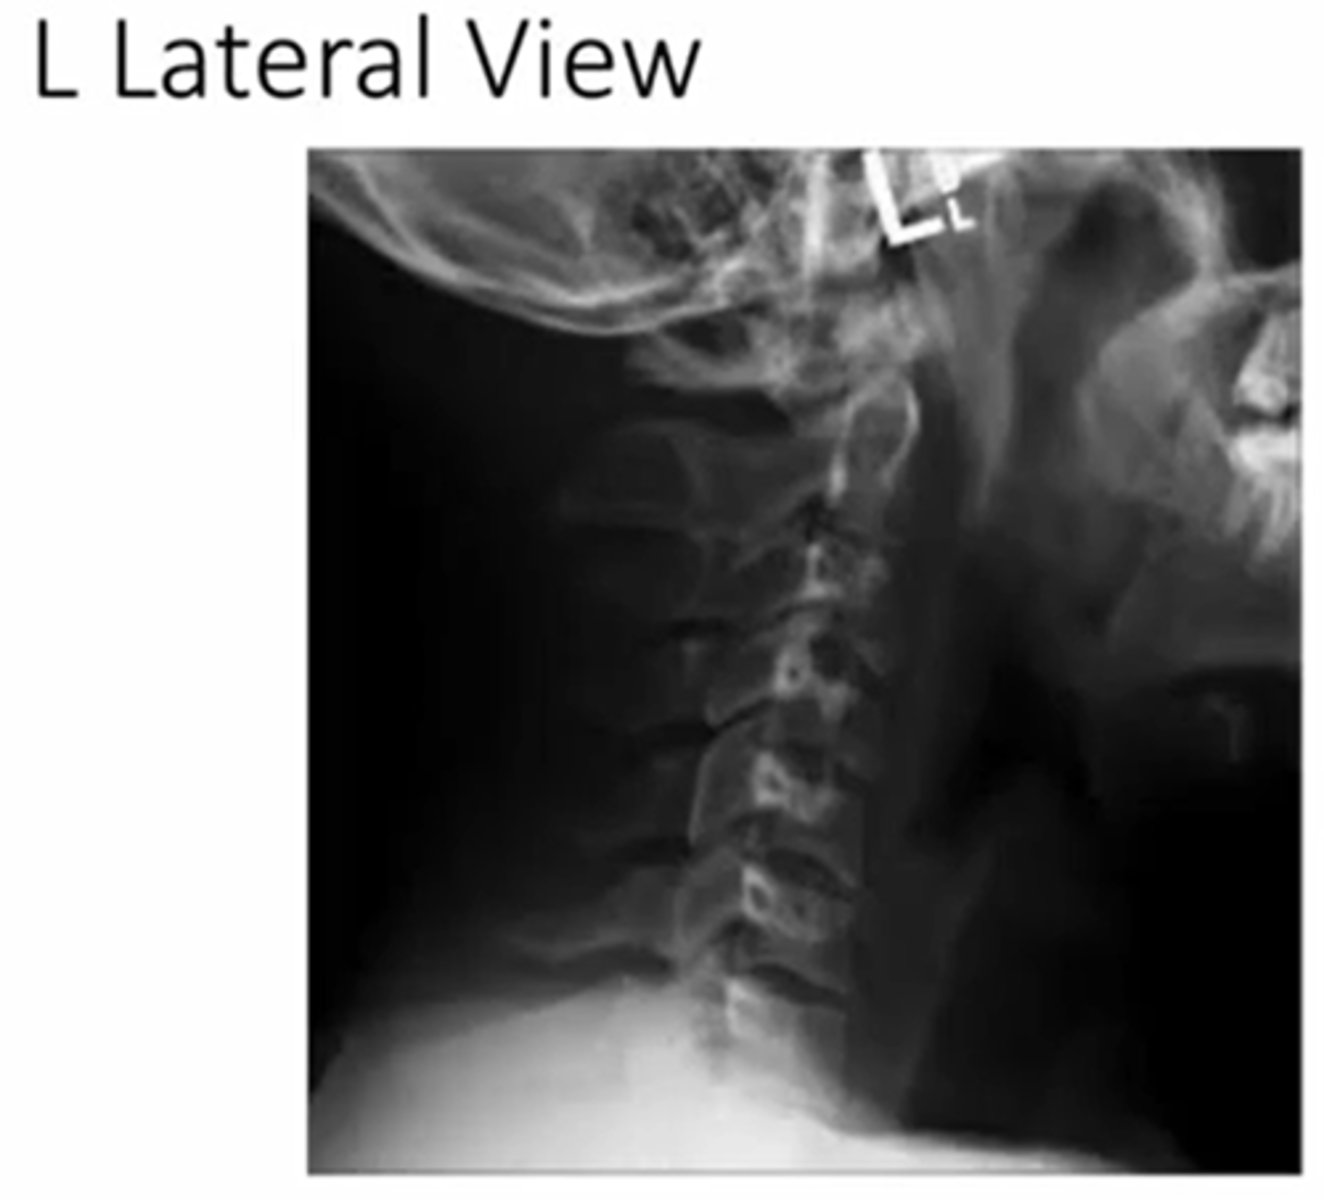

when looking at the c/s what is the better view to see the disc height

lateral

what view of the c/s can you see the pedicles?

AP

what are you looking for during AP view of CS

after a trumatic event to the C/S what image will you expect them to take

AP open mouth view

what does a normal AP x-ray of C1-2 look like

what does the spinolaminar line, anterior and posterior vertebral line look like

purple anterior

posterior: blue

spinolaminar line: green

between blue and green is the spinal cord

what does a left oblique cs image look like